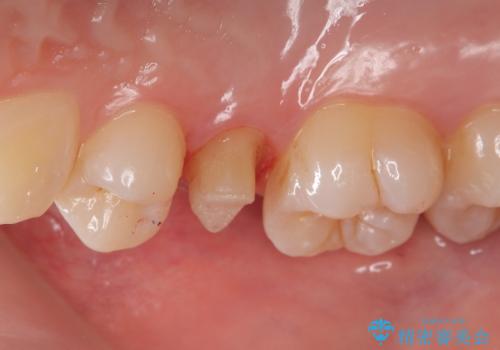

右上5番目の歯が根管治療途中となっており、前医院にて根管が狭く治療が難しいと言われてしまいセカンドオピニオンで当院にいらっしゃいました。

精密根管治療を行うこととしました。

右上5番レントゲン写真上では根管が確認しずらく、根管の狭窄が予想されました。マイクロスコープを使用し、根尖部まで器具を到達させ十分根管洗浄を行うことができました。